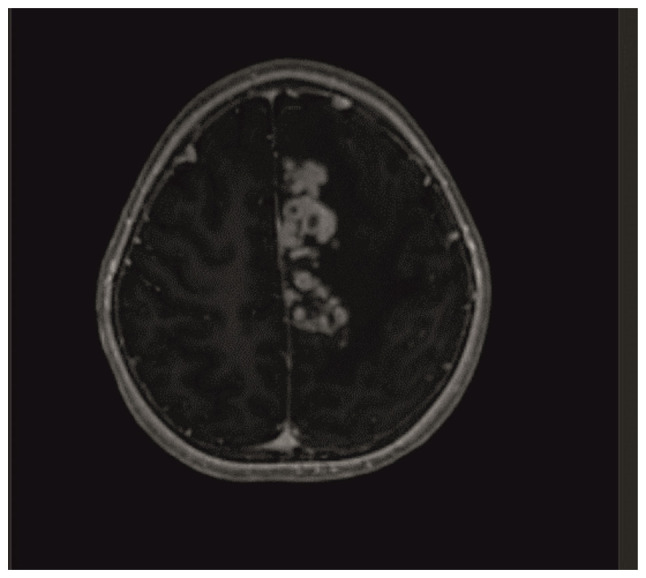

颅内结核瘤是中枢神经系统结核(TB)最严重的并发症之一,发病率相对较低。在颅内结核瘤病例中,患者在接受抗结核治疗时可能出现药物毒性和/或免疫重建炎症综合征(IRIS)。目前的研究报告了一名7岁的颅内结核瘤女性患者在治疗过程中出现药物性肝毒性和IRIS。在患者随访期间,出现抗结核药物性肝炎,导致两次停药。在治疗的第七个月,颅脑MRI显示结核瘤病变的进展。考虑到IRIS或治疗失败的可能性,重新开始使用类固醇和非肝毒性抗结核药物治疗。通过类固醇和抗结核治疗,病变几乎完全消退,神经功能缺损也得到了缓解。由于抗结核药物可能产生的副作用,特别是IRIS,应密切随访接受治疗的患者,IRIS是在免疫系统恢复过程中作为免疫重组反应而发展起来的。

Intracranial tuberculoma represents one of the most severe complications of central nervous system tuberculosis (TB), with an incidence that is relatively low. In cases of intracranial tuberculoma, patients may develop drug toxicity and/or immune reconstitution inflammatory syndrome (IRIS) while receiving anti-TB treatment. The current study presented the case of a seven-year-old female patient with intracranial tuberculoma who developed drug-induced hepatotoxicity and IRIS during the course of treatment. During the follow-up of the patient, anti-TB drug-induced hepatitis developed, which led to the discontinuation of the drug twice. In the seventh month of treatment, cranial MRI showed the progression of tuberculoma lesions. The possibility of IRIS or treatment failure was considered and the treatment was restarted with steroids and non-hepatotoxic anti-TB drugs. With steroid and anti-TB treatment, the lesions regressed almost completely and the neurological deficit regressed. Patients receiving treatment should be followed up closely due to the possible side effects of anti-TB drugs, especially IRIS, which develops as an immune restructuring response during the recovery of the immune system.